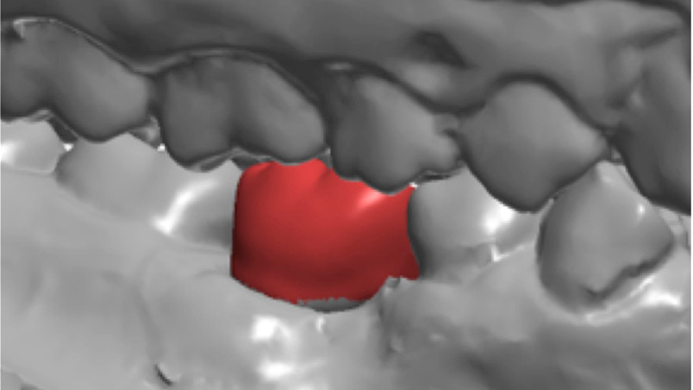

Clinical case: # 46 implant placement & GBR using i-Gen membrane for significant vertical resorption & mixed bone defect

- Courtesy of Dr. Iulian Filipov, Romania -

AnyRidge, mandibular posterior, i-Gen, resorption, bone defect, bone regeneration, space management, #46, GBR, Dr. Iulian Filipov